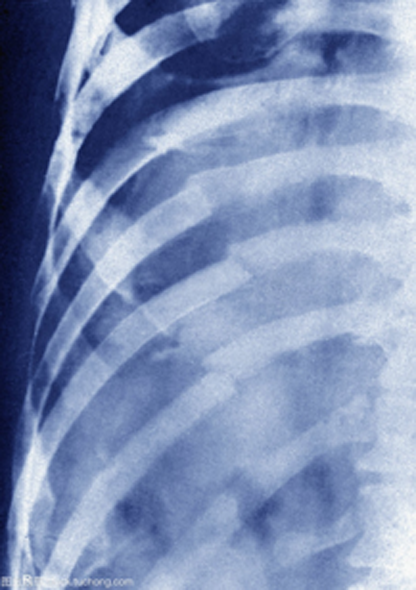

明显的骨折X线检查就可以明确诊断,而且它简便易行、费用低,是骨折的首选检查方法。但是,X光片检查并非十全十美,它只能显示照射范围内所有器官重叠在一起的影子,并不能将各种器官区分开。而且 人体骨骼的形态不一、前后重叠,加之有时骨折出现错位等情况,X线检查容易漏诊、误诊。此外局部出血还会掩盖骨折,过1-2周出血吸收后,骨折处变得清晰—这也是医生让患者短期复查的原因。